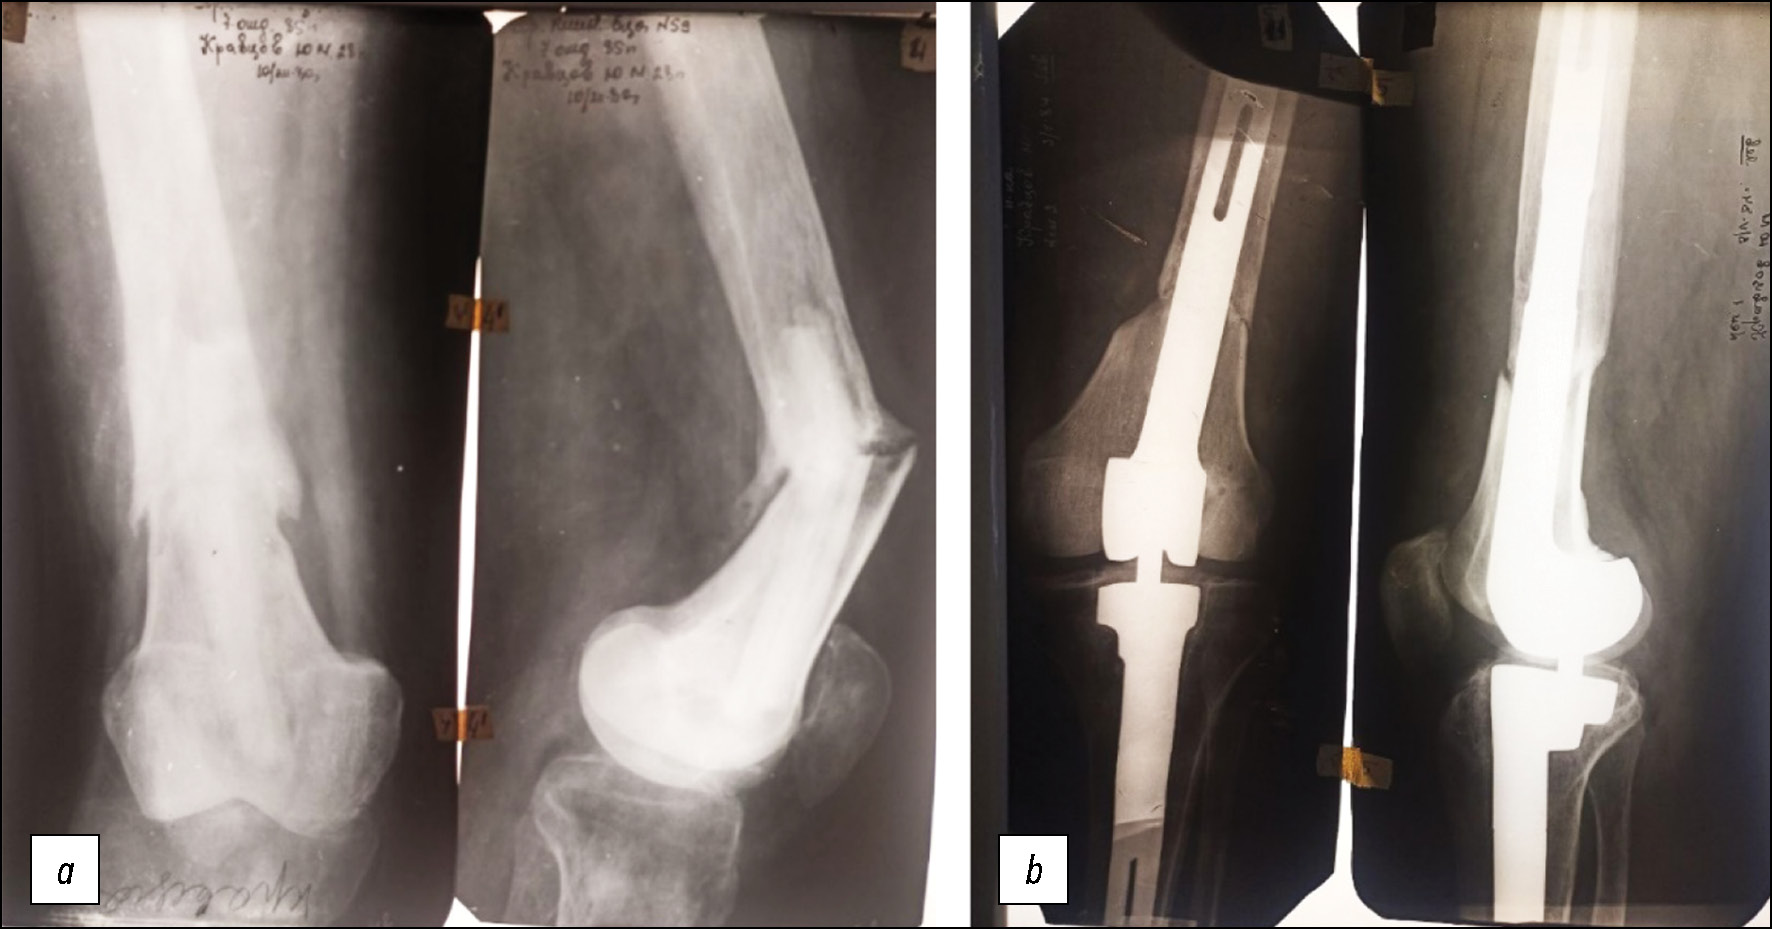

В 1984 г. больной вновь был госпитализирован в отделение ортопедии нашей клиники, и ему была выполнена операция замены аллотрансплантата дистального конца бедренной кости в комбинации с межмыщелковым эндопротезированием коленного сустава (рис. 3).

Рис. 3. Рентгенограммы коленного сустава: a — до, b — после имплантации аллотрансплантата дистального конца бедренной кости и межмыщелкового эндопротезирования коленного сустава.

Fig. 3. Radiographs of the knee joint: a — before, b — after implantation of an allograft of the distal end of the femur and interstitial knee replacement.

Сразу после операции восстановлена полная стабильность сустава и начата разработка движений, которые достигли 180–70 градусов. Пациент передвигался с помощью костылей, дозированно нагружая оперированную конечность. Через полгода наступило сращение трансплантата с костью и разрешена ходьба без дополнительных средств опоры. Боли в суставе не беспокоили.